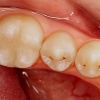

Dentiinikaaries on dentiinikihti osaliselt haarav defekt e. hambaauk milline ulatub emaili all hambaluusse. kuid pulbi kaitseks jääb veel küllalt kahjustamata kudet. Võrreldes emailiga on dentiin vähem kaltsifitseerunud ja sisaldab mikroskoopilisi õõnsusi (tuubuleid), mistõttu allub kergemini hapete ja mikroobide mõjule ning kaaries kulgeb seal kiiremini.

Sügav dentiinikaaries on pulbi lähedusse ulatuv sügav karioosne defekt, mille juures dentiini kiht pulbi kaitseks on jäänud väga õhukeseks. Sellise kahjustuse puhul võib esineda kaebus valule, mis tekib teravamaitselise toidu ja külma-kuuma ärritusele.